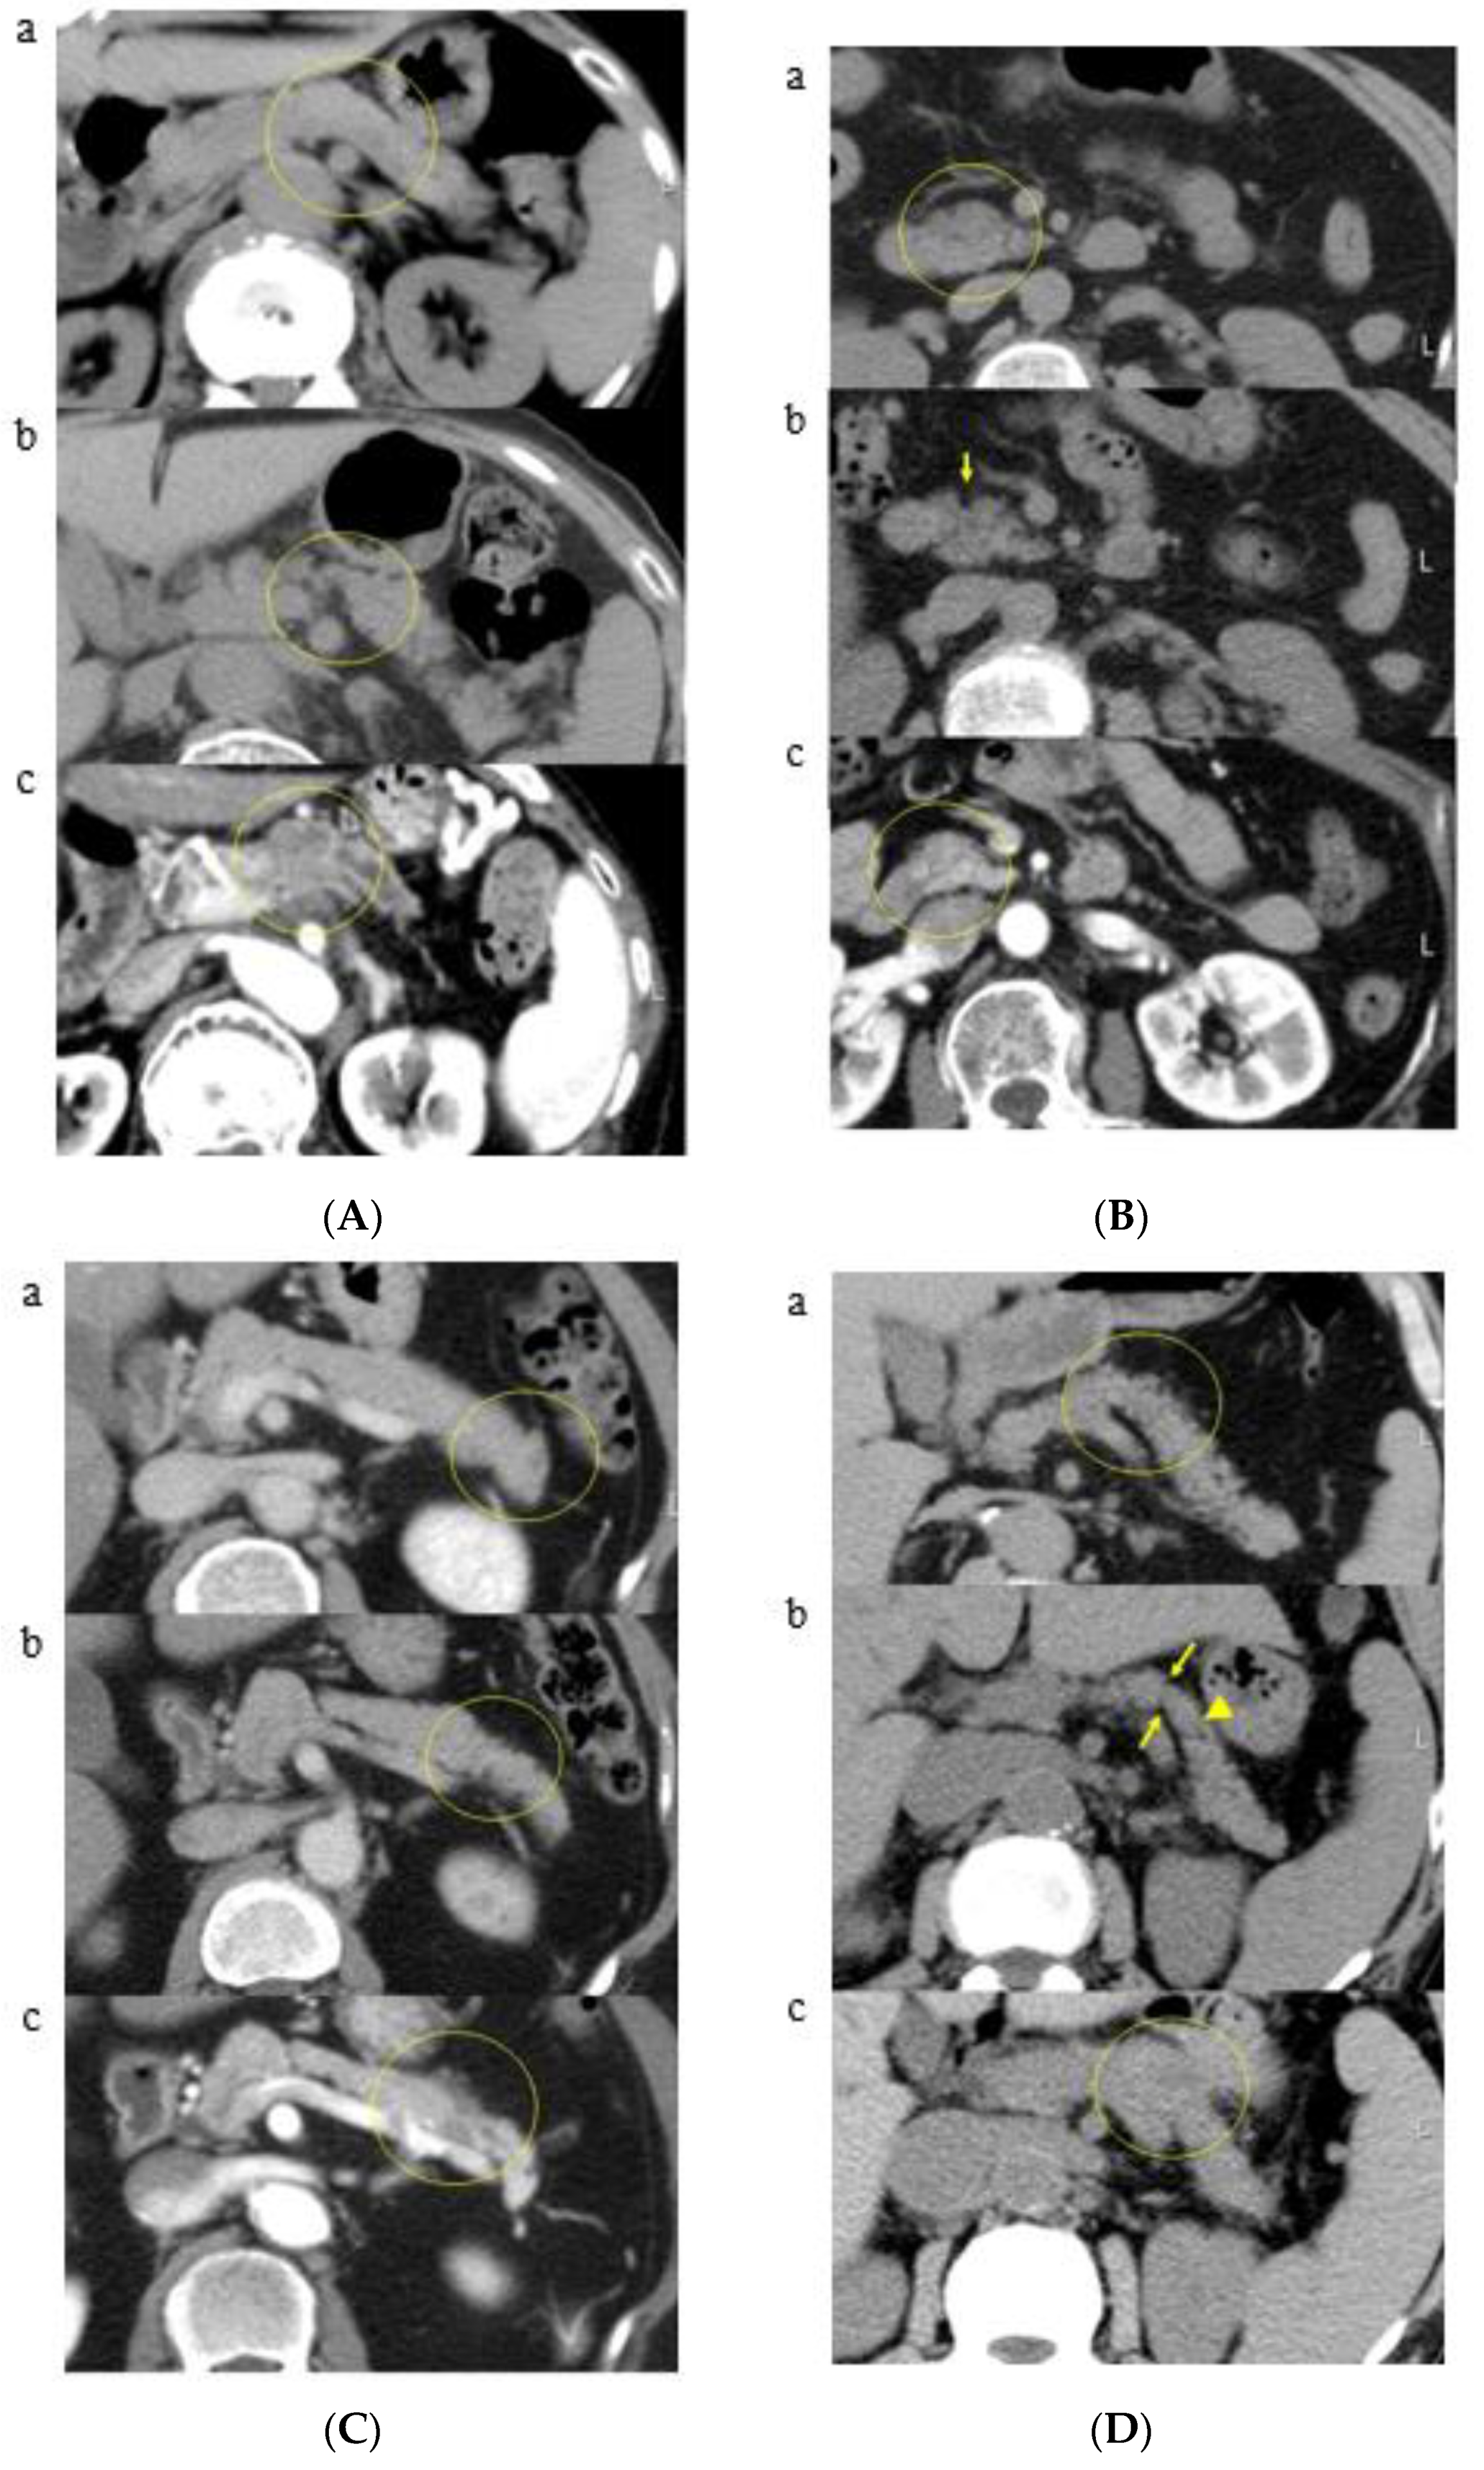

3.2. A Representative Case and Classification by Specific Abnormality of the Pancreas

3.3. Time to Development of Pancreatic Cancer